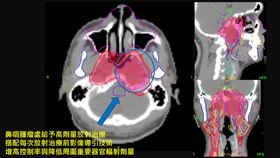

鼻塞、複視竟4期鼻咽癌 白袍救人放大絕

48歲的蔡先生,五年前因脖子莫名腫大、長期鼻塞且出現...